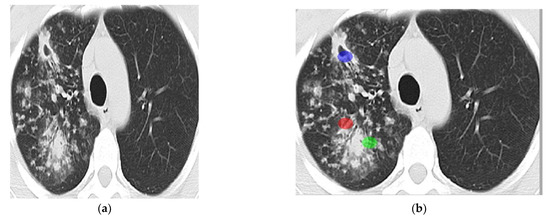

Due to the unavailability of expensive CT scan devices and the lack of expert human experts, TB is comparatively in high numbers in developing countries of Asia. In Pakistan, CT scan devices are rarely available in private clinics; however, Govt has facilitated public hospitals. After struggles, 100 abnormal (TB infected) and 100 normal CT scan images of lungs were acquired from Bahawal Victoria Hospital (BVH) Bahawalpur, Department of Radiology. Tuberculosis-affected and normal images are shown in Figure 2.

Figure 2. (a): Tuberculosis affected lung image and (b): Normal lung CT image.